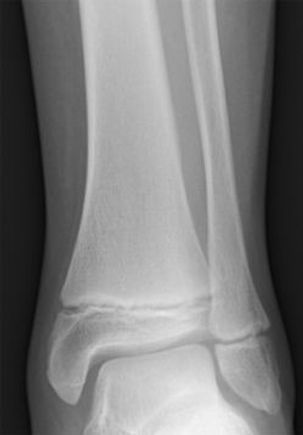

X-ray of tibia (left) and fibula (right) in a child showing two growth plates